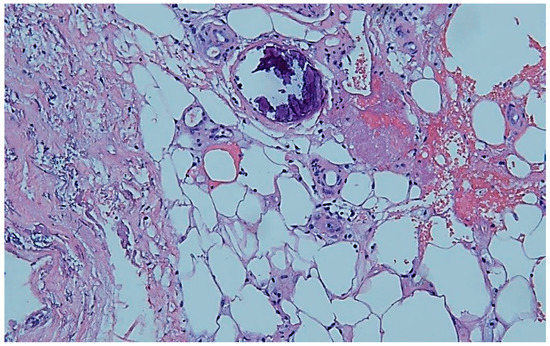

Despite use of a good wound therapy, including an attempt to use negative-pressure wound therapy, we could achieve only a poor improvement. This led us to the decision to take a histological sample. Subepithelial increase of small vessels with inflammatory alteration and distinct hemosiderosis were found in the biopsy. Subsequently, a typical calcification of a small vessel was described in the upper corium, primarily pointing to calciphylaxis (Figure 2). There was no evidence of a local vasculitis or a metastasis of the known breast cancer.

Figure 2. Histopathology: Typical calcification of a small vessel in the upper corium. By courtesy and permission of Prof. Dr. P. von den Driesch, Dept. of Dermatology, Stuttgart General Hospital.